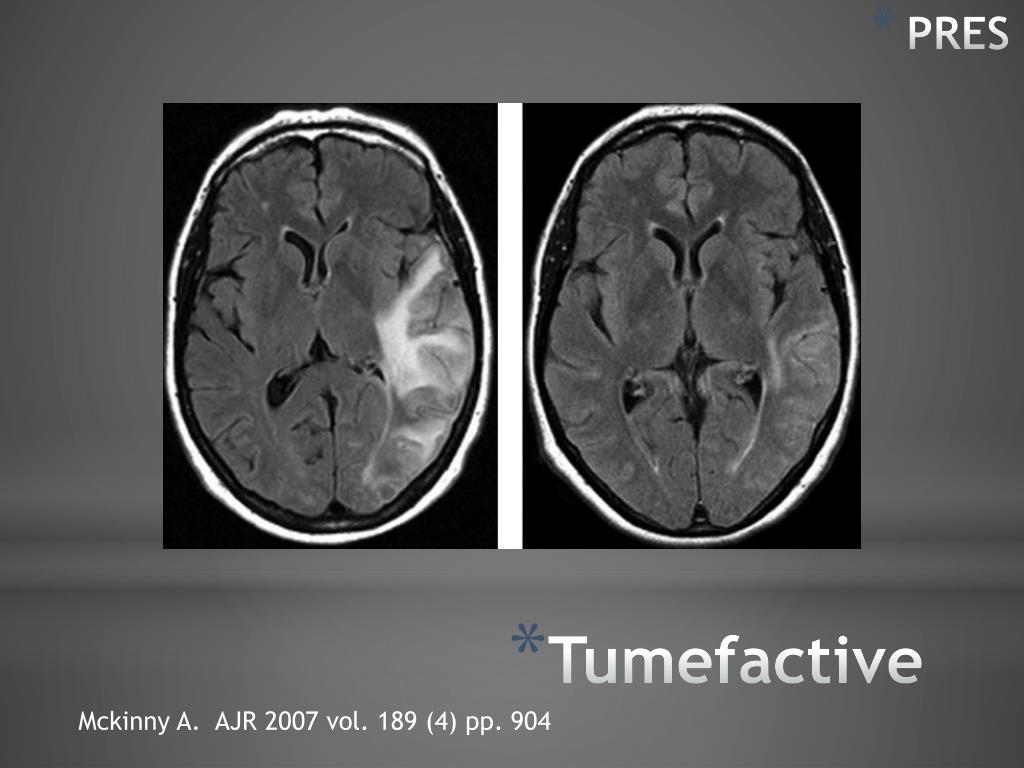

32. PRES Tumefactive Mckinny A. AJR 2007 vol. 189 (4) pp. 904

19. Japanese Encephalitis Amogh N. Hegde, MD, FRCR RadioGraphics2011; 31:5–30